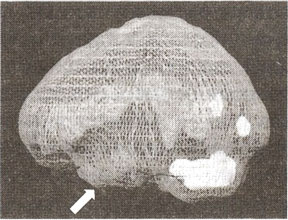

Наш опыт играет колоссальную роль, делая нас теми, кто мы есть. Височные доли, располагаясь в обоих полушариях головного мозга, прямо за глазницами и под височными костями, хранят воспоминания и образы, помогая нам осознавать себя самими собой.

Нарушение функций височных долей случаются чаще, чем думали раньше. Вы, наверное, заметили, что многие из перечисленных симптомов прежде считались психологическими, в то время как на самом деле они вызваны биологическими причинами. Височные доли находятся в очень уязвимой части мозга в височных ямках (впадинах), за глазницами и за височными костями. На передней стенке впадины находится выступающий острый край сфеноидной кости, который нередко травмирует лобные доли даже при легких травмах головы. (Было бы лучше, если бы Господь надел на этот край какую-нибудь защиту.) Из-за того, что височные доли размещаются во впадине, с пяти сторон окруженной костными выступами (спереди, сзади, справа, слева и снизу), они могут пострадать от удара по голове, нанесенного практически под любым углом.